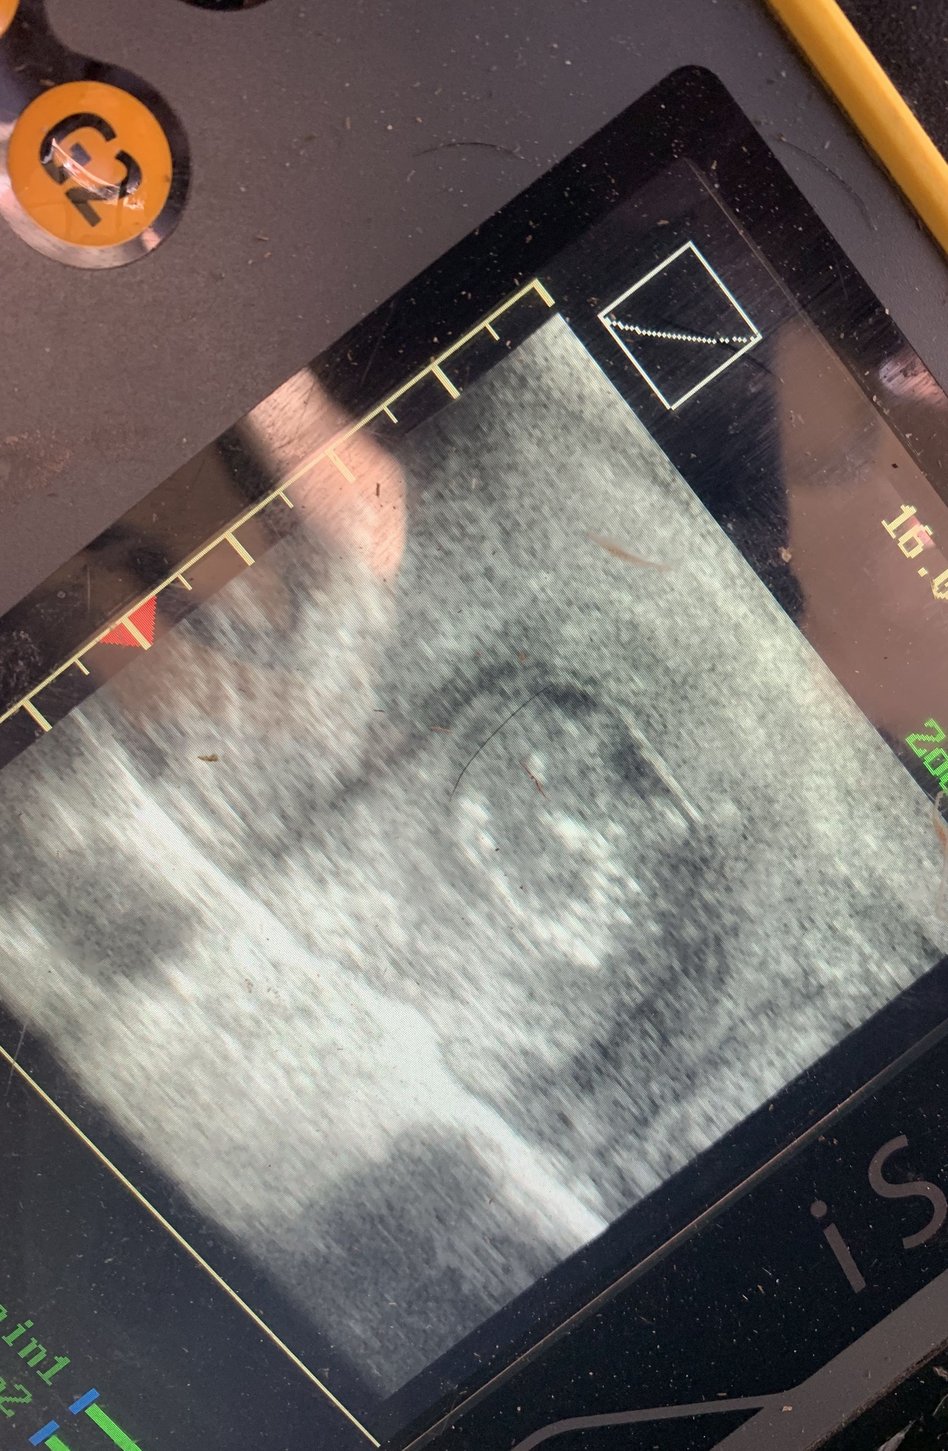

En effet, l'échographie ne sert pas uniquement à confirmer une gestation. Elle permet également de visualiser l'invisible : l'état des ovaires, la vitalité de l'embryon ou la détection précoce d'éventuelles pathologies.

L'intérêt de ce TP dépasse la simple manipulation technique. L'objectif pédagogique est de former les élèves au pilotage de la reproduction. En détectant les gestations plus tôt (dès 30 jours), l'éleveur peut prendre des décisions rapides : ré-inséminer, adapter l'alimentation ou surveiller une bête spécifique.